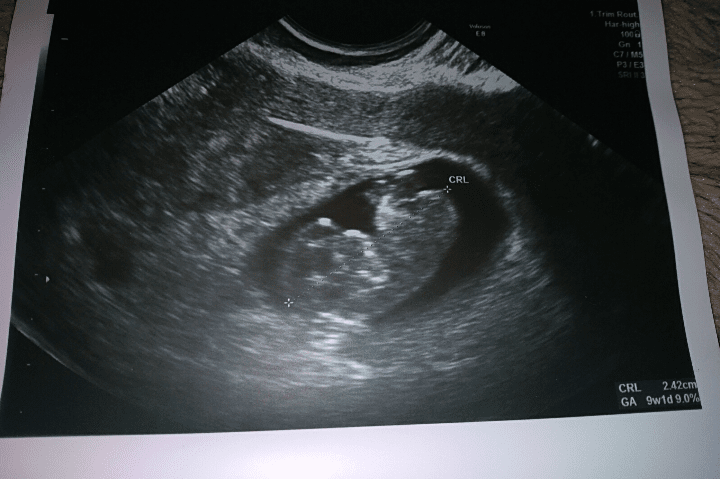

Dziś pokaże Wam moje maleństwo [emoji173]️

Kropek to już nie jest [emoji23]

Maluszek ma 2,4 cm [emoji7]

Według OM 9+4

Według Usg 9+1

Krwiak się sporo wchłonął. Dalej mam leżeć, ale został tylko mały krwiak więc najgorsze niebezpieczeństwo za nami.

Jestem taka szczęśliwa [emoji3059] :D